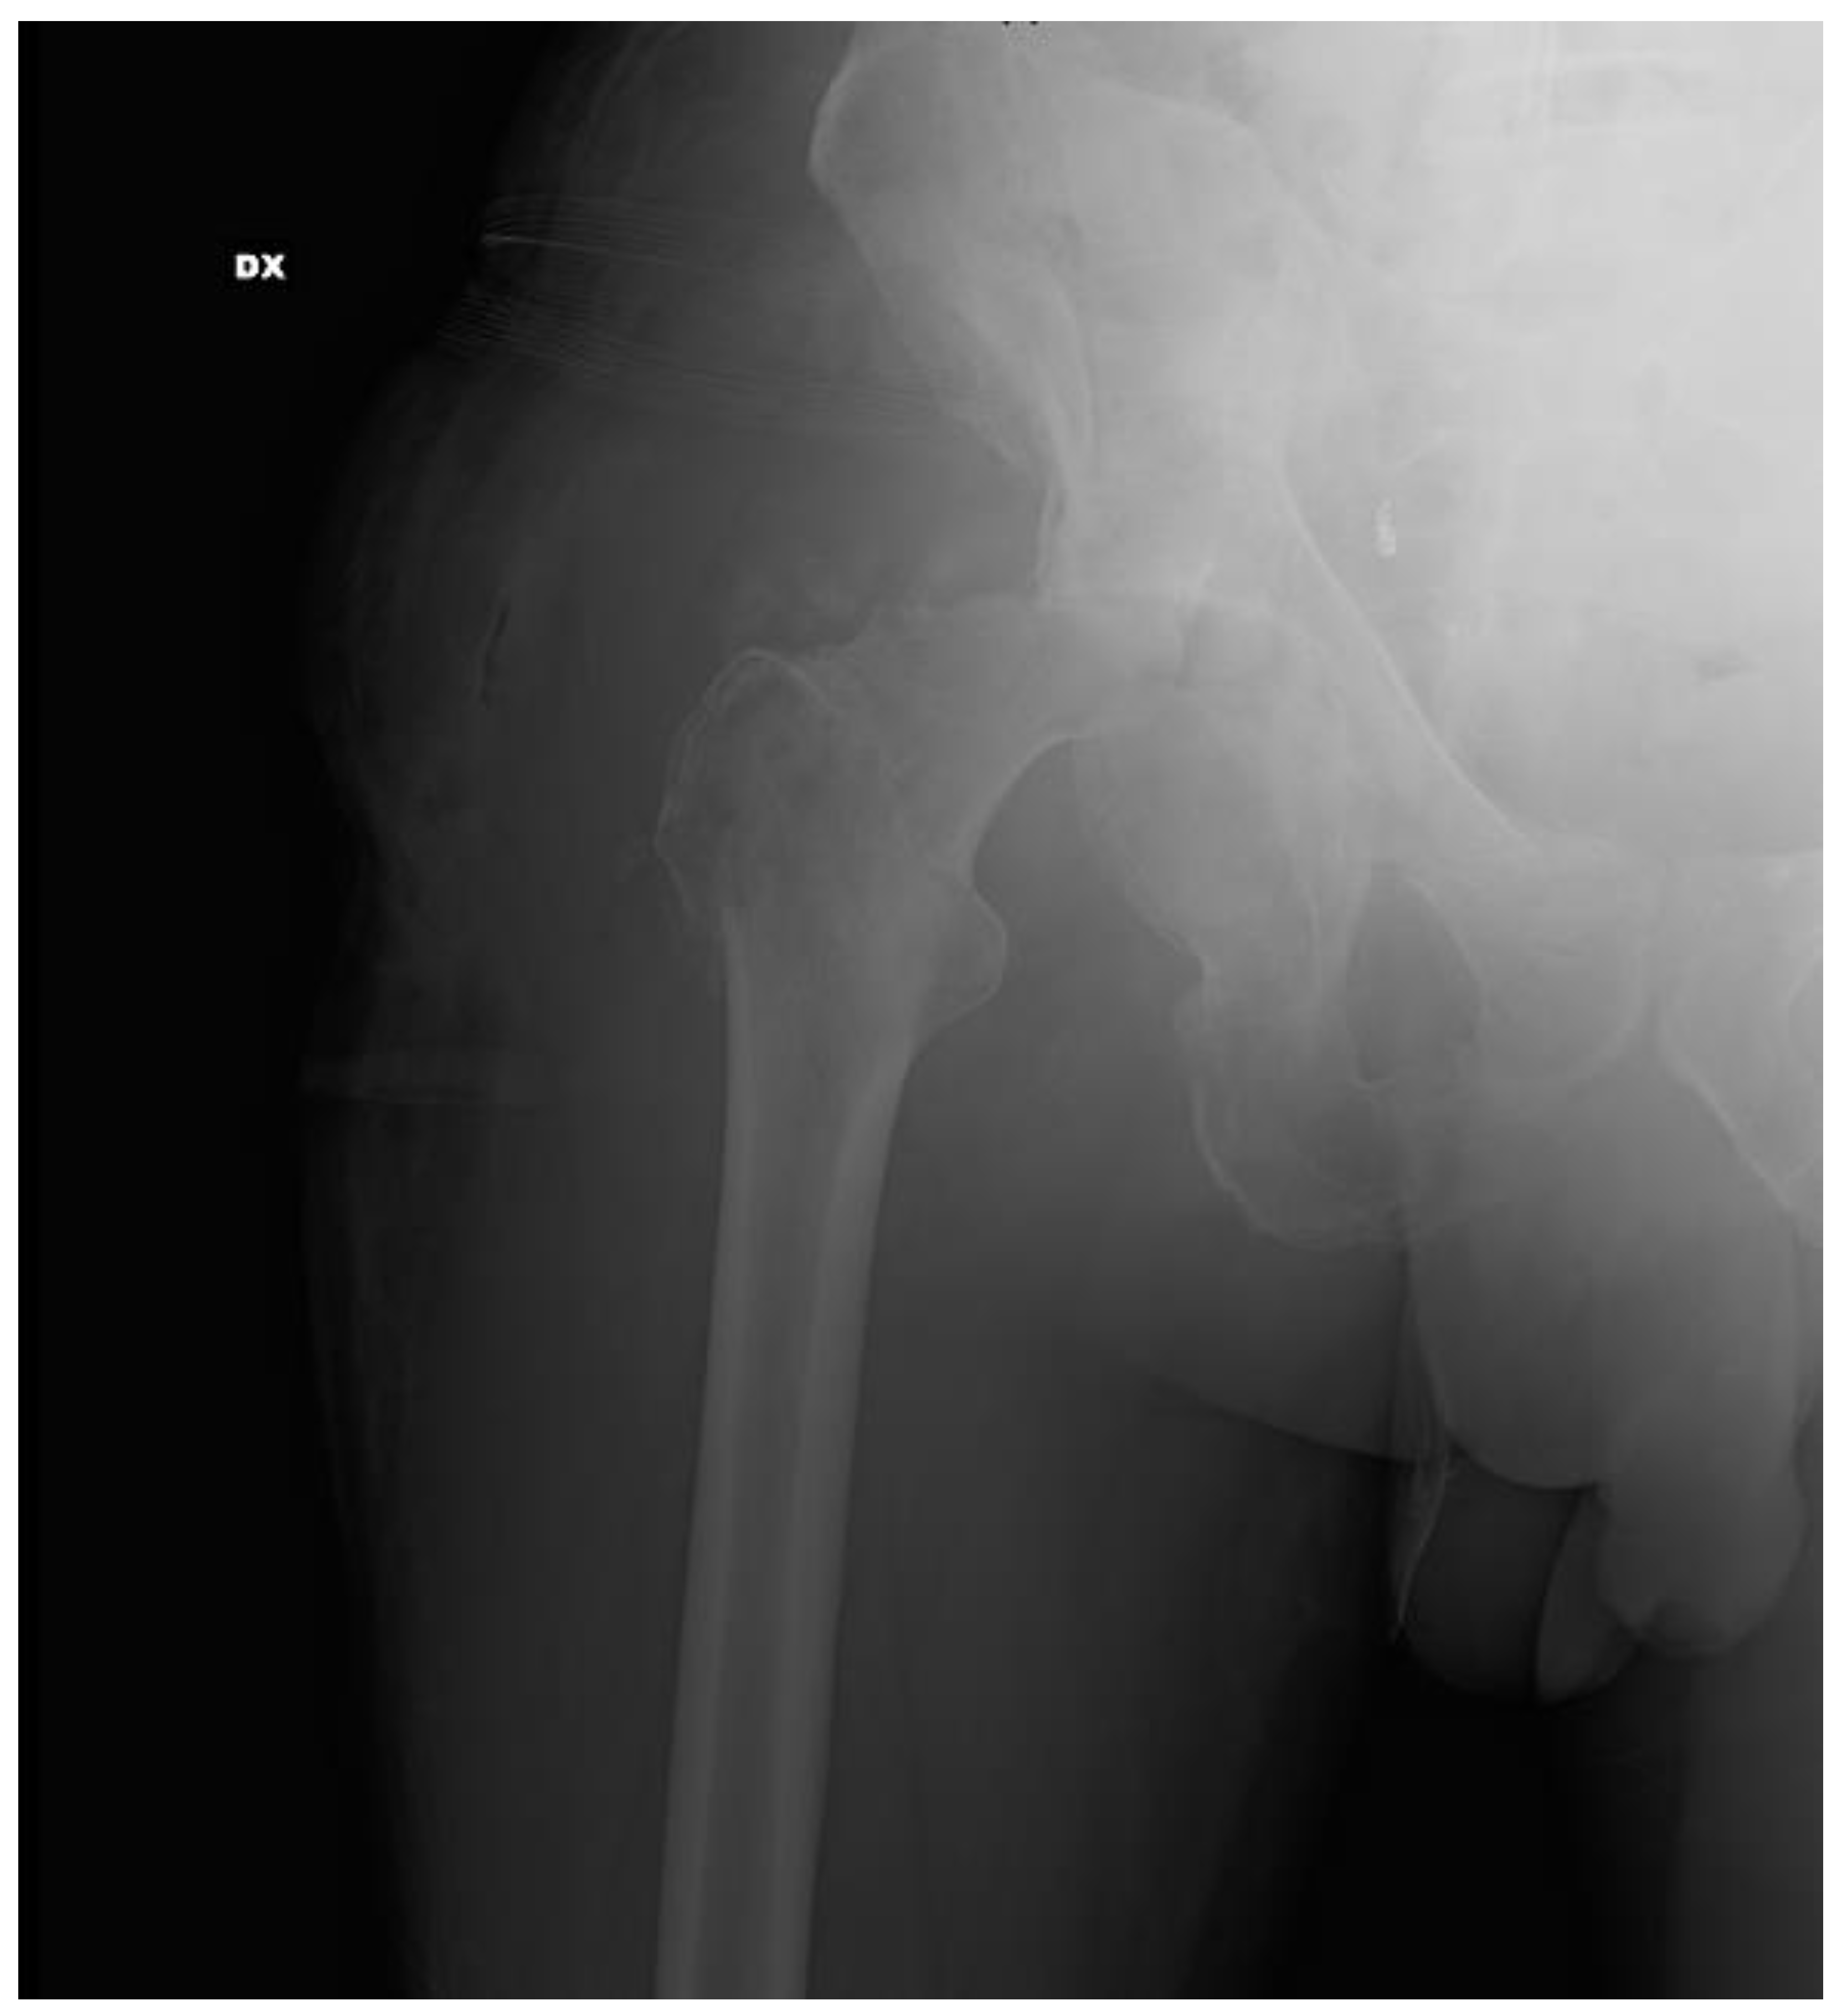

2. Case Report